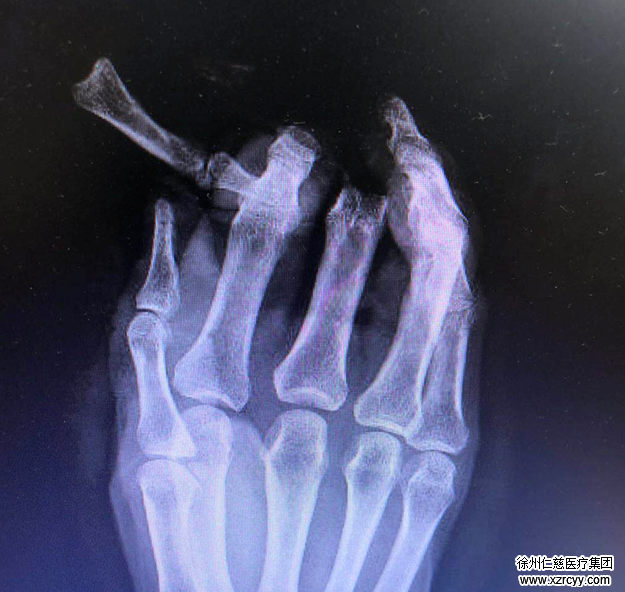

急诊手外科熊祖国医生接诊,检查发现患者右手示中指损伤极其严重,中指近节脱套性离断,指伸屈肌腱均从前臂肌腹抽出,双侧指动脉及指神经均自近侧长段抽出,离断指体碾挫伤严重,大部分青紫瘀斑;右示指于近节近端平面及远节多平面离断,而且远节指体系脱套离断,离断指体碾挫伤严重。右手背皮肤缺损。

熊医生为患者申请了急诊绿色通道,患者被紧急送入手术室行再植手术。由于患者右示中指离断指体血管抽出并碾挫伤严重,而且缺损至指总动脉,术中手术小组予前臂切取皮下“Y”型静脉,移植桥接、重建指总动脉及示中指指动脉,恢复中指离断指体及示指近中节指体血供;示指远节脱套离断指体血管缺损,再次于前臂切取皮下静脉桥接重建远节脱套离断指体血供。同时保存了中指的指间关节,可以使患者右手的功能得到最大程度的恢复。手术历经5小时,右手示中指离断指体再植成功。

术中摄片情况:保存了中指的指间关节,可使手指功能得到最大程度恢复。